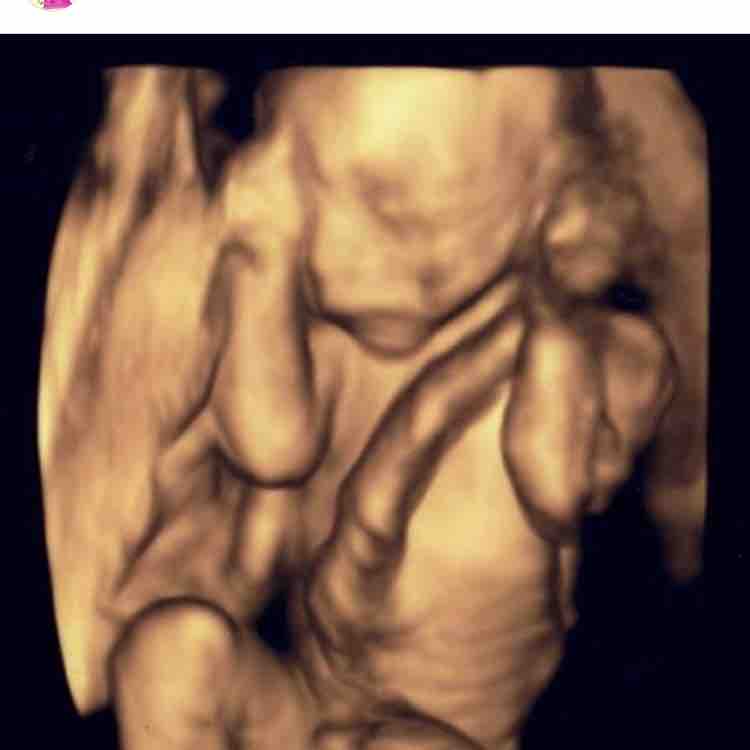

4dエコーで初めて見たわが子の顔 先生が撮った最高の1枚 たまひよ

赤ちゃんの3d 4dエコー写真 実際の顔と比較してみたら似てた 旅するダンサー自由記

画像あり エコー写真と実際の顔を徹底比較 4dエコー撮影おすすめ時期はいつ キラキラままライフ

3d 4d超音波外来 六本木一丁目駅直結の丸茂レディースクリニック 産科 婦人科 4d 3dエコー検査